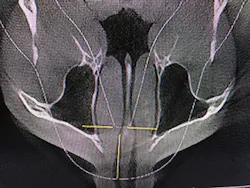

Figure 4: Maxillary and mandibular retrusion.

Figure 8: Deviated nasal septum and narrowed airway

Figure 9: 95% obstructed posterior airway due to extremely enlarged tonsils

After identifying Danny’s history and evaluating the clinical signs, we moved to screening and testing. We recommended a home sleep test for his airway and breathing problems, as well as a Doppler auscultation and CBCT imaging for the TMD and occlusal issues.

The Doppler auscultation revealed reciprocal click on the left temporomandibular joint. The CBCT revealed normal joint anatomy, nasal airway obstruction with a slight deviated septum, and approximately 95% tonsillar obstruction in the posterior throat region. These findings led us to the conclusion of a positive airway/breathing disorder, with a Piper Stage I right temporomandibular joint and Piper Stage IIIa left temporomandibular joint.